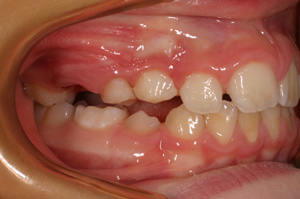

.... Spontaneo riposizionamento dei molari permanenti! Dopo 8 mesi viene tolto il REP! Contenzione con dispositivo elastodontico che guida in eruzione i denti permanenti! Durata: 24 Mesi Inizio Aprile 2006 - Fine Aprile 2008 A fine terapia si cerchera' di evitare un trattamento ortodontico fisso, se cio' sará possibile, finalizzando il caso con un positioner individualizzato!